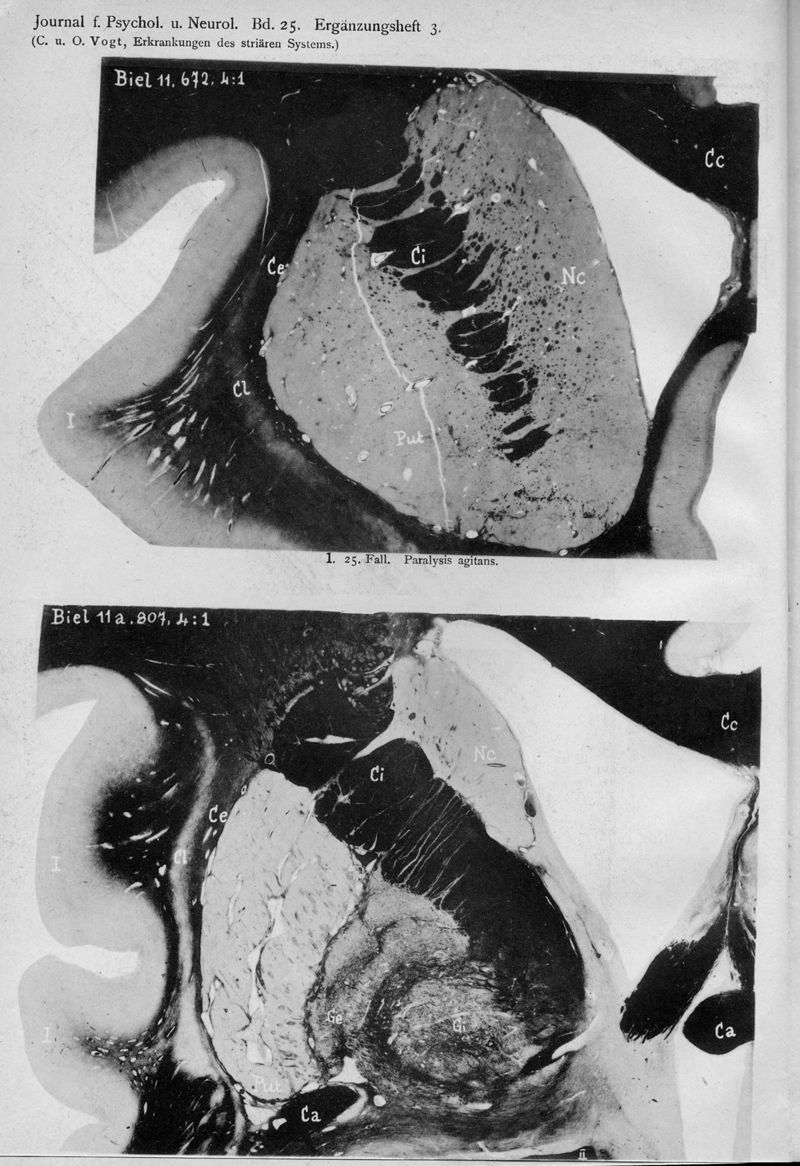

VOGT, Cécile / VOGT, O.

In : Journal für Psychologie und Neurologie,

1920, Vol. 25, pp. 627-846